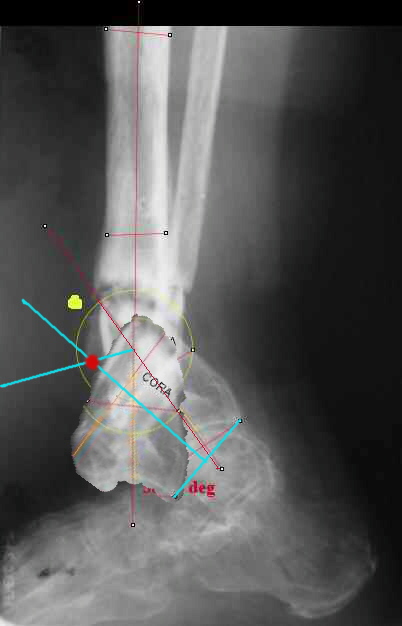

I played with your image using some orthopedic software we have been developing for digital

image analysis.

What you see marked up is the intercept of two mid-line tool centre lines, used to define the CORA. An angle tool gives the angular deformity and a circle tool is applied to show that a correction around the CORA through the old # will restore alignment without much translation.

TDVC> I played with your image using some orthopedic software

TDVC> we have been developing for digital image analysis.

I definitely have to learn more about this. THX in advance.

TDVC> a correction around the CORA through the old # will restore

TDVC> alignment without much translation.

Maybe my "embedded software" is obsolete but it hints me to place hinges at the yellow point - this must result with alignment and some lengthening without translation. What do you think?

Re the CORA.:

I think that if you locate the hinge at that site and then you rotate the foot about this point with out distraction you will be perfectly lined up. If you distract in the axis of the proximal tibia then rotate, it should still work (the hinge should still be located in the mid tibial axis). But, if you distract out of that axis then you will get translation. Does that make sense?

Hi Alex:

I looked at your image. I presume your yellow marker is the hinge axis? I think this should be at the CORA.